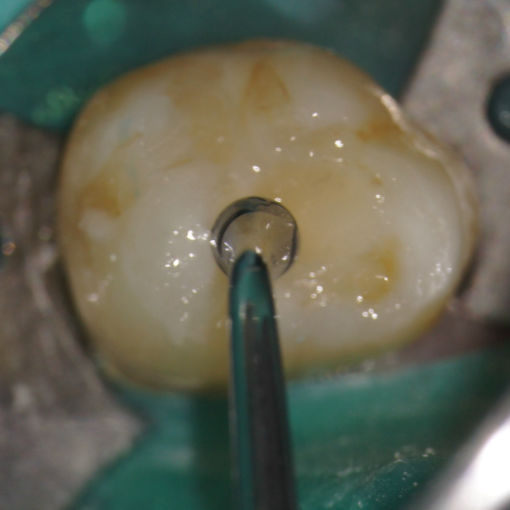

En el centro de tu diente hay pulpa. La pulpa es una colección de vasos sanguíneos que ayuda a construir el diente que lo rodea. La infección de la pulpa puede ser causada por un traumatismo en el diente, caries profundas, fisuras o procedimientos dentales repetidos. Los síntomas de la infección pueden identificarse como lesión visible o hinchazón del diente, sensibilidad a la temperatura o dolor en el diente y las encías.

Si experimenta alguno de estos síntomas, su dentista probablemente le recomendará un tratamiento no quirúrgico para eliminar la pulpa enferma. Esta pulpa lesionada se retira y el sistema de conducto radicular se limpia y sella completamente. La terapia del conducto radicular generalmente involucra anestesia local y puede completarse en una o más visitas, dependiendo del tratamiento requerido. El éxito de este tipo de tratamiento ocurre en aproximadamente el 90% de los casos. Si su diente no es susceptible al tratamiento de endodoncia o la posibilidad de éxito es desfavorable, se le informará en el momento de la consulta o cuando se presente una complicación durante o después del tratamiento.